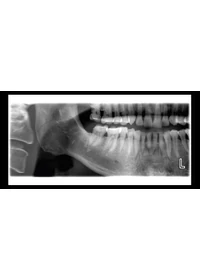

Autófókusz – a mindenkori tökéletes panorámakép elkészítéséhez

Az egyedülálló autófókusz jellemző automatikusan pozícionálja a fokális réteget a beteg középső metszőfogainak kisdózisú feltáró képeit használva. A beteg anatómiájának jellegzetes pontjait használja az elhelyezés kiszámításához, ezzel gyakorlatilag lehetővé téve a hibamentes betegpozícionálást és drámaian csökkentve a felvételek ismétlésének szükségességét. Az eredmény a mindig tökéletes panorámakép.